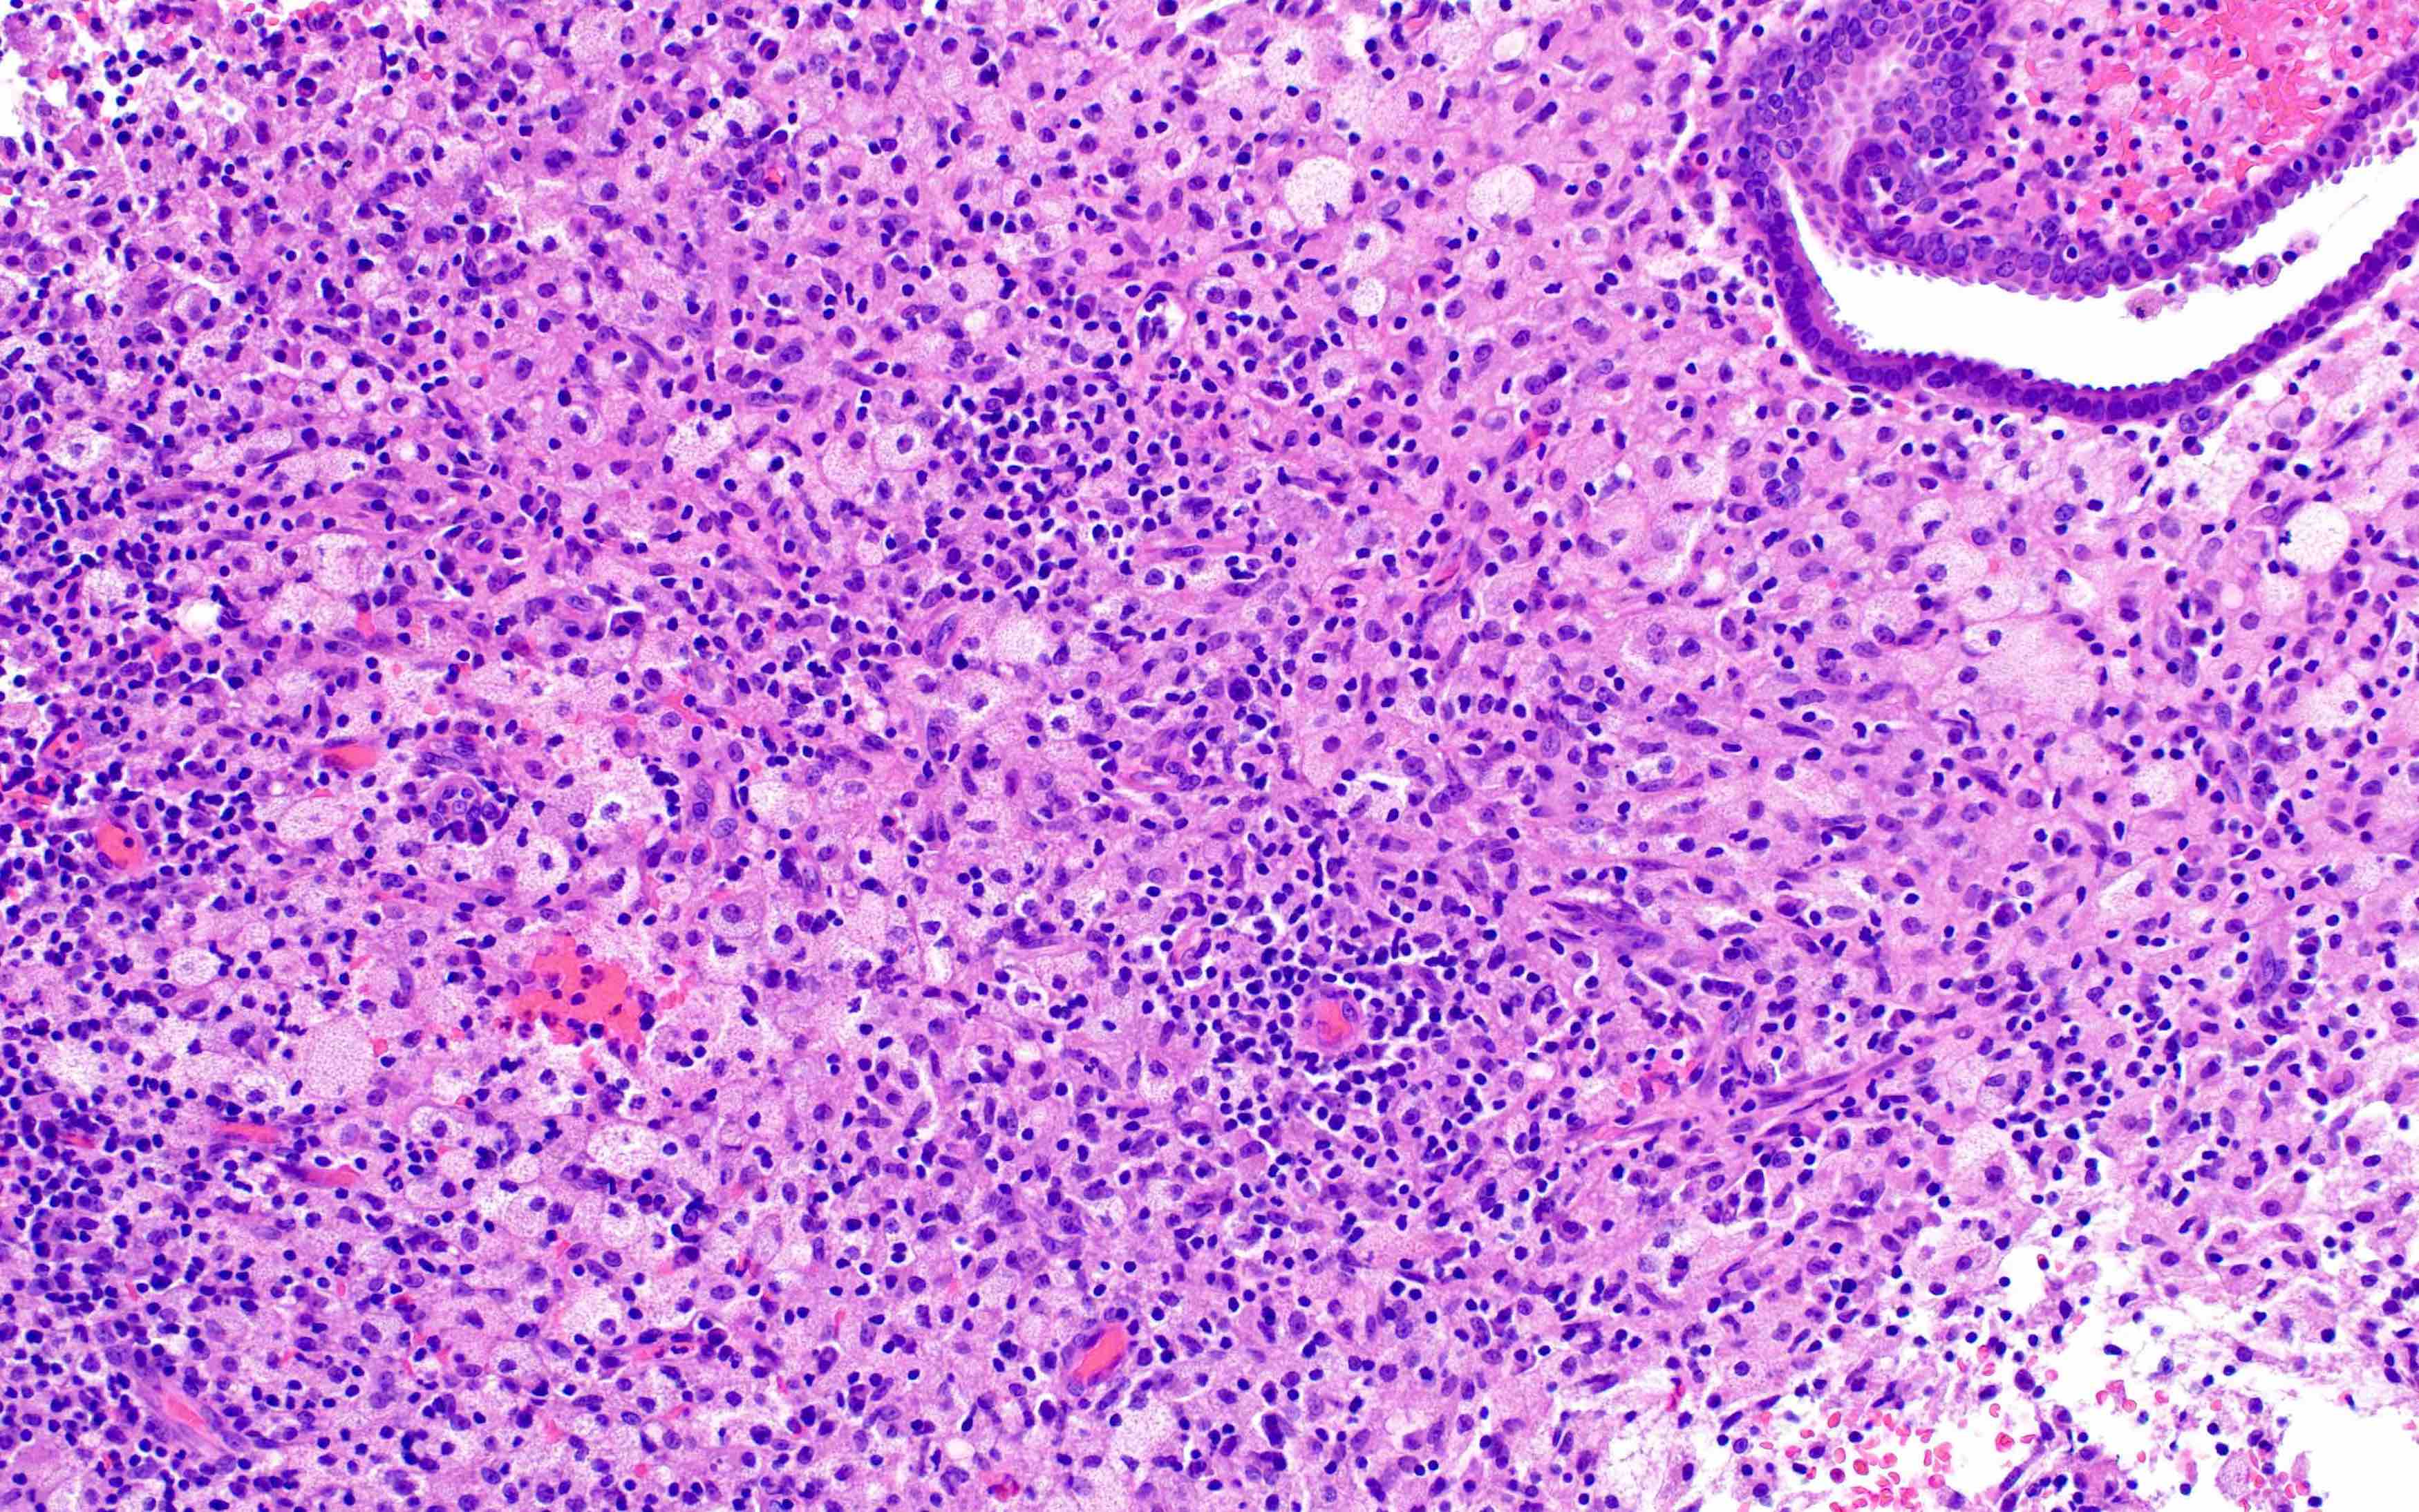

Microscopic (histologic) images

Contributed by Stephanie L. Skala, M.D. and Yuri Tachibana, M.D.

Chronic endometritis

Xanthogranulomatous endometritis